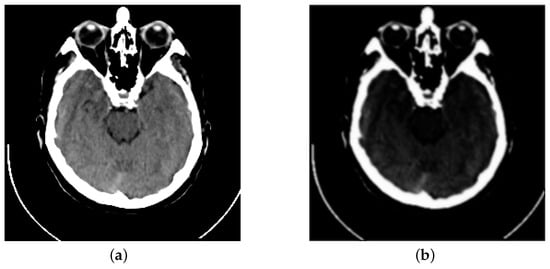

Inspired by previous works, we propose a fusion strategy, which is based on the visual saliency-based method (VSM) [34]. We use VSM to calculate the weight maps of computed tomography (CT) images. Then, based on these CT image weight maps we obtain the weight maps of magnetic resonance imaging (MRI) images. Figure 1 presents the visual saliency map of CT image on the image pair “Acute stroke speech arrest-3”. It is obviously observed that VSM of CT can remain the features of dense structures such as implants and bones. Meanwhile, the low-resolution soft tissues are reduced.

Figure 1. Example of a CT image and its visual saliency map. (a) The source CT image of “Acute stroke speech arrest-3”. (b) The visual saliency map of this CT image.